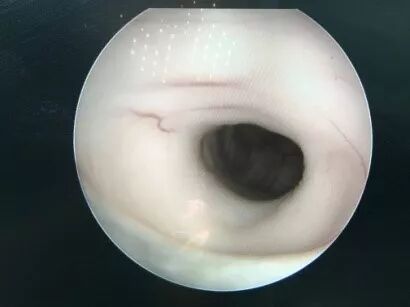

![]()

二次内镜探查可见造瘘口及导水管都是通畅的,考虑患儿存在交通性脑积水,医生使用贝朗蛇牌proGAV2.0分流管 进一步为患儿做了脑室腹腔分流术。